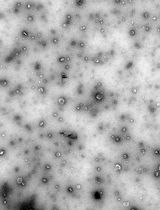

7. Using a 200 μL pipette and tip, add 1 mL of polymer solution dropwise to the stirring water. You should see the liquid turn somewhat milky/white, but not fully opaque. No visible aggregation should be observed (Figure 1A).

Figure 1. Representative images of nanoparticles and crosslinked nanoparticles. (A) Nanoparticle solutions at various concentrations and sizes (<200 nm). Note that for in vivo applications, larger nanoparticles are associated with greater complement activations; solutions that are completely opaque (like milk) may have large aggregates. Analyze a sample via dynamic light scattering to confirm. (B) The inversion test evaluates if the material has formed a gel. Another sign is the bubbles (blue arrows): gelled solutions tend to have bubbles trapped at the surface, whereas for liquids, the bubbles will eventually travel to the bottom of the inverted tube.